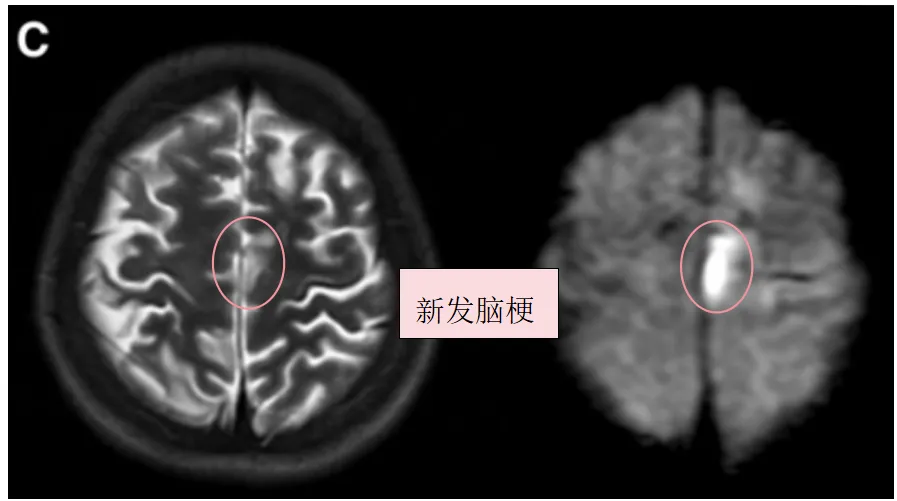

确诊后一个月,小玉因构音障碍和右腿无力再次入院。MRI检查结果令人揪心:她左额叶出现了新的脑梗死灶。

然而灾难并未停止。入院三天后,影像检查显示她左侧颞叶再次出现新发脑梗死。一次又一次的打击,让小玉的神经功能迅速衰退,MRS评分达到4分——重度残疾。

图C:术前T2、DWI序列显示左额叶新发展的脑梗死

图D:入院3天后术前T2、DWI序列显示左侧颞叶进一步新发脑梗死